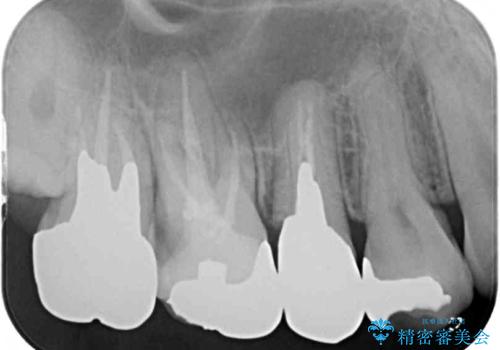

- ものが挟まるとのことで来院された患者様です。

一度は治療せずに放置していましたが、1年後のメインテナンスの際に悪化していることが分かったことから、補綴治療を行うこととしました。

神経を抜いてある歯はむし歯が進行しても痛みを感じることがないため、気がついたときには著しくむし歯が進行している可能性があります。

早めの対応とすることで、抜歯を回避できることはもちろん、外科処置などの本来必要のない処置を行わずに対処することができました。